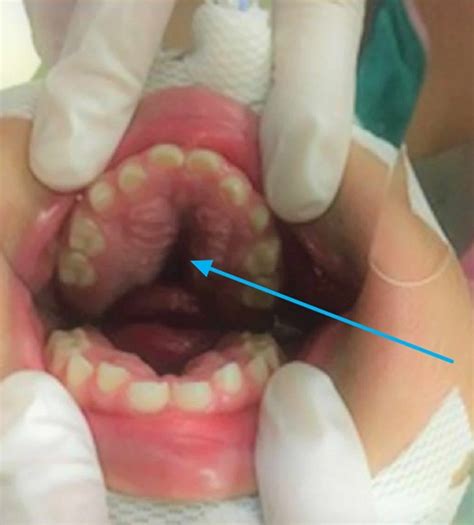

Understanding the intricacies of a high arched palate is crucial for dental professionals, speech therapists, and individuals experiencing related issues. A high arched palate, also known as a high vaulted palate or ogival palate, refers to a condition where the roof of the mouth is unusually high and narrow. This anatomical variation can have significant implications for oral health, speech development, and overall well-being.

A high arched palate is characterized by a steeply curved roof of the mouth, which can affect the alignment of teeth, the shape of the jaw, and the overall structure of the face. This condition is often congenital, meaning it is present at birth, but it can also develop due to environmental factors such as thumb-sucking, tongue-thrusting, or prolonged use of a pacifier.

Identifying a high arched palate typically involves a visual examination by a dental professional. During this examination, the dentist or orthodontist will assess the shape and height of the palate, as well as the alignment of the teeth and the position of the tongue. In some cases, additional diagnostic tools such as X-rays or 3D imaging may be used to gain a more comprehensive understanding of the condition.